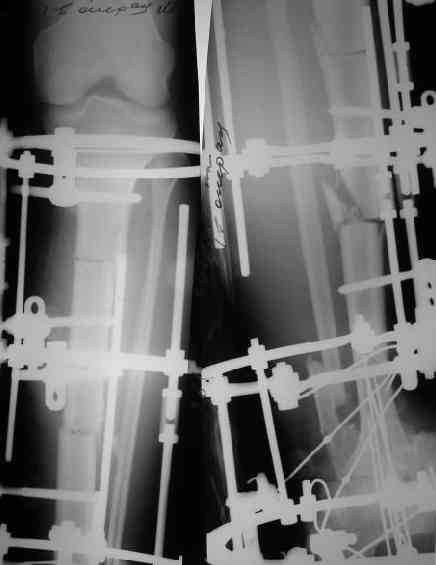

Решили не связываться с остеосинтезом, а сделать сразу берцово-пяточный блок. Снимки в приложении.

По завершении удлинения, наверно, заштифтуем.